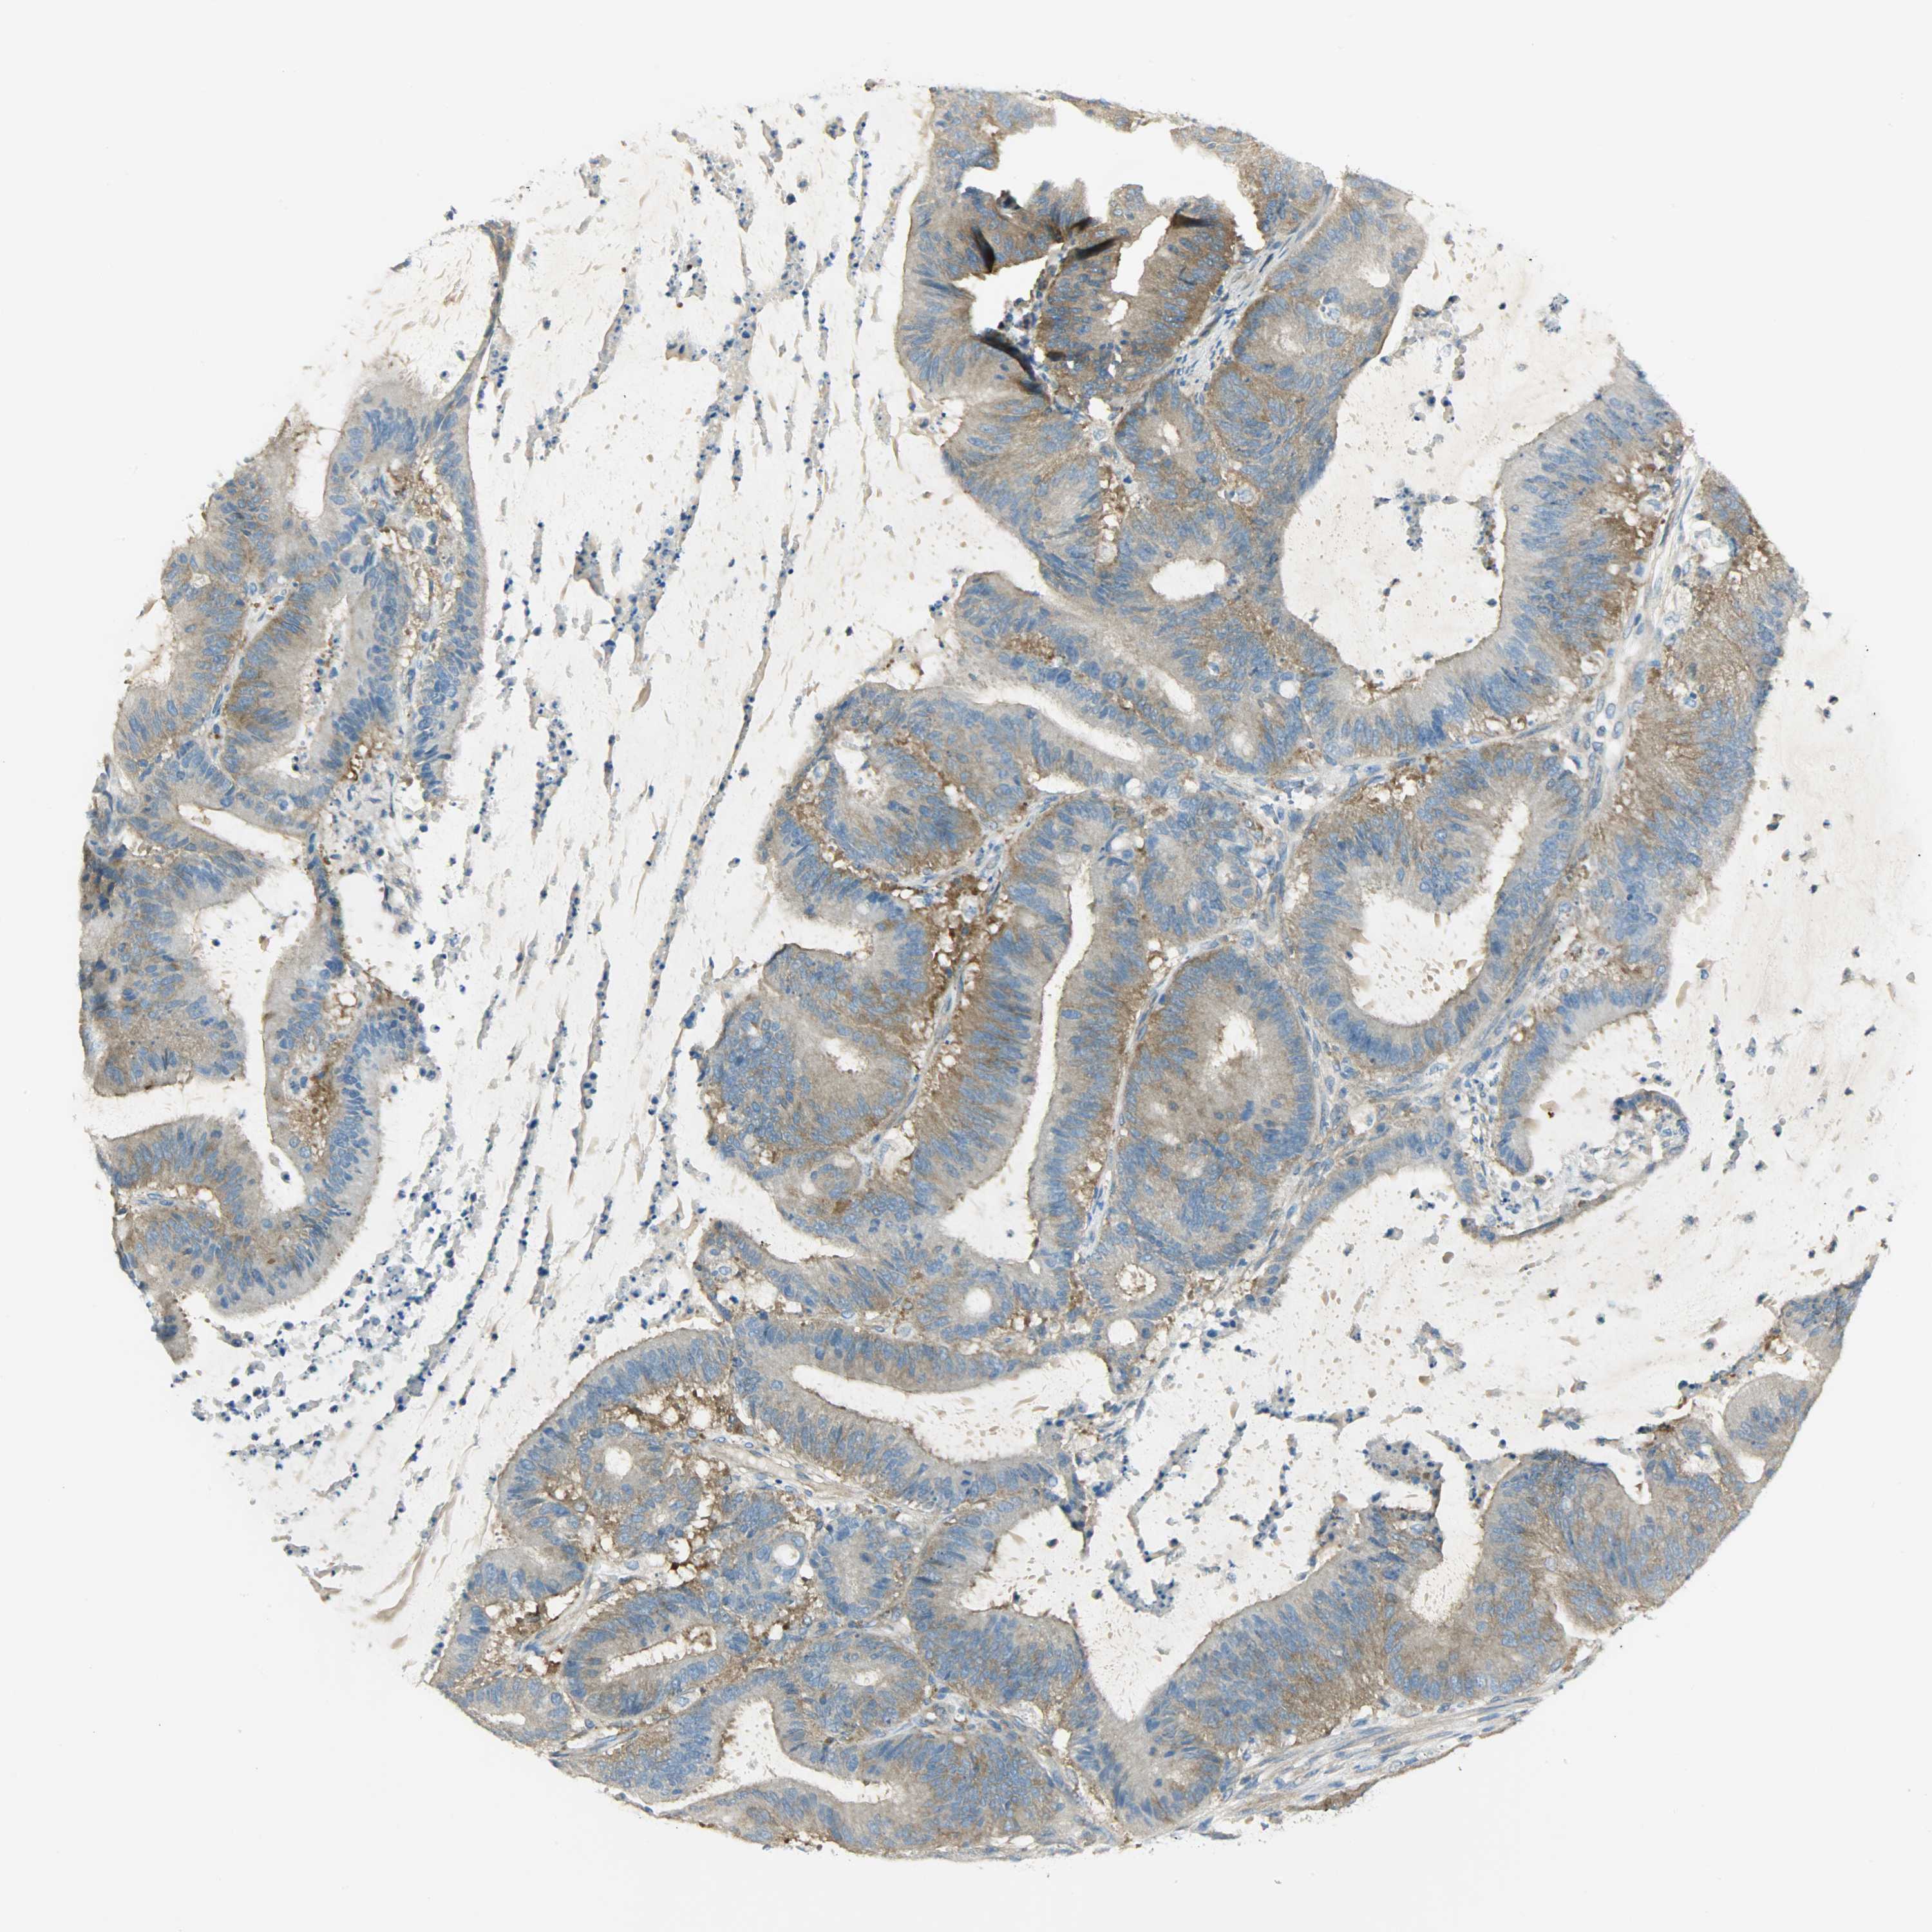

LIVER CANCER - Protein expressioni

A mouse-over function shows sample information and annotation data. Click on an image to view it in a full screen mode. Samples can be filtered based on level of antibody staining by selecting one or several of the following categories: high, medium, low and not detected. The assay and annotation is described here.

Note that samples used for immunohistochemistry by the Human Protein Atlas do not correspond to samples in the TCGA dataset.

Antibody stainingi

Antibody staining in the annotated cell types in the current human tissue is reported as not detected, low, medium, or high, based on conventional immunohistochemistry profiling in selected tissues. This score is based on the combination of the staining intensity and fraction of stained cells.

Each image is clickable and will lead to virtual microscopy that enables deeper exploration of all samples and also displays staining intensity scores, fraction scores and subcellular localization as well as patient and tissue information for each sample.

Antibody HPA004926

Staining

High

Medium

Low

Not detected

Intensity

Strong

Moderate

Weak

Negative

Quantity

>75%

75%-25%

<25%

None

Location

Nuclear

Cytoplasmic/membranous

Cytoplasmic/membranous,nuclear

Cholangiocarcinoma

Carcinoma, Hepatocellular, NOS